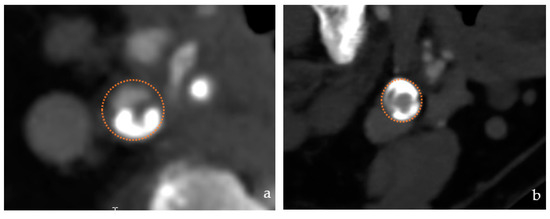

- Lesion type: target lesions were categorized as eccentric, concentric, or carotid near occlusion (>90° stenosis) (Figure 5).

Figure 5. Lesion type (a) Eccentric lesion (b) concentric lesion.